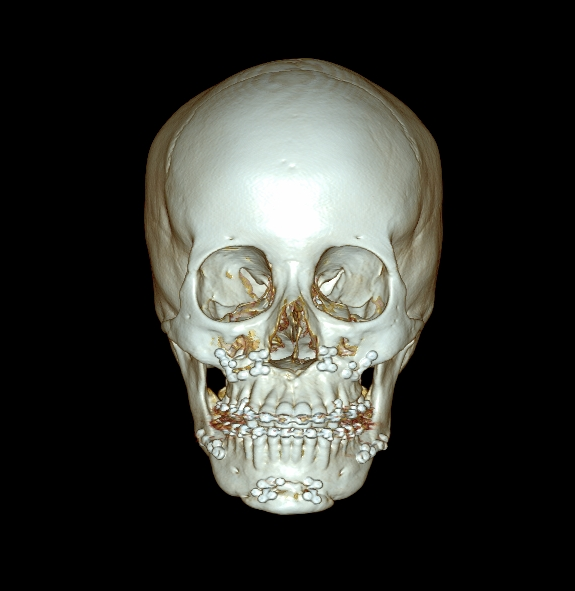

수술 전 3D CT로 핀 위치,

골유합 상태, 주변 신경/혈관

위치를 정확히 분석

3D 시뮬레이션과 수술 계획 수립

3D CT 촬영 및 시뮬레이션, 원장님 정밀 상담 후

환자 맞춤형 수술 방향 결정